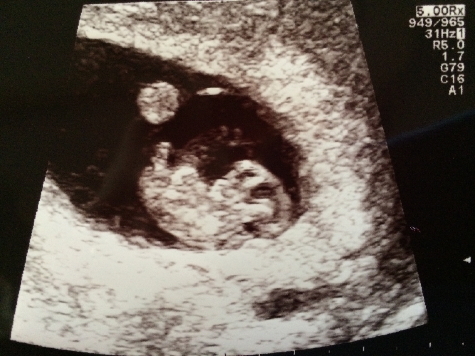

I know it's early (9 weeks), but you probably understand my impatience...... So for fun for now, what would be your best guess, a boy or a girl? (based on nub/skull/Ramzi)

Don't worry...... I won't order a wardrobe or anything yet until I am 100% sure ;)